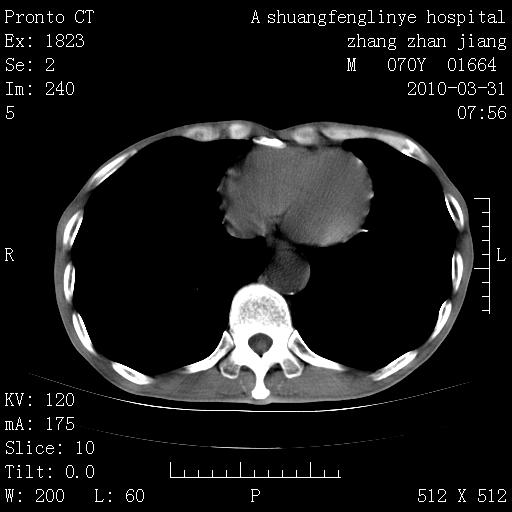

标题: CT25450:肺结核?

双上肺继发型tb并左上空洞形成,主动脉冠脉钙化。

1)两肺上叶继发性肺结核并左肺上叶空洞形成。2)冠状动脉及主动脉钙化。